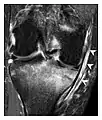

The greater tuberosity of the humerus is also an illustrative location of occult fractures. The osseous injury may follow seizures, glenohumeral dislocation, forced abduction, or direct impaction. They are commonly discovered on MRI in symptomatic patients with suspicion of rotator cuff tear. Coronal images are best suited for detection. They appear as crescentic oblique lines surrounded by a bone marrow edema pattern (Figure 5). The rotator cuff must be inspected since associated ligamentous lesions are common. In the ankle, malleoli and tarsal bones should be checked carefully for any cortical disruptions and radiolucent lines that may reveal a fracture. Awareness of the exact location of the pain will help direct the attention of the interpreter when searching for very subtle signs of fracture (Figure 6).[1]

a

b

Figure 6: Subtle anterior talar fracture in a 39-year-old man presenting with ankle pain after a fall. (a) Anteroposterior radiograph shows a subtle oblique radiolucent line through the talus (white arrows). (b) Sagittal CT reformation confirms the presence of an anterior talar fracture with cortical offset (black arrow). Avulsion fractures, which consist of a detached bone fragment resulting from a ligament or tendon pulling away from the bone, may also present with subtle radiographic signs. Tiny osseous fragments near the presumed attachment site of a ligament suggest this diagnosis. Common sites are the lateral tibial plateau (the Segond fracture), the spinal tuberosity of the tibia resulting from anterior cruciate ligament avulsion, and the ischial tuberosity.[1]